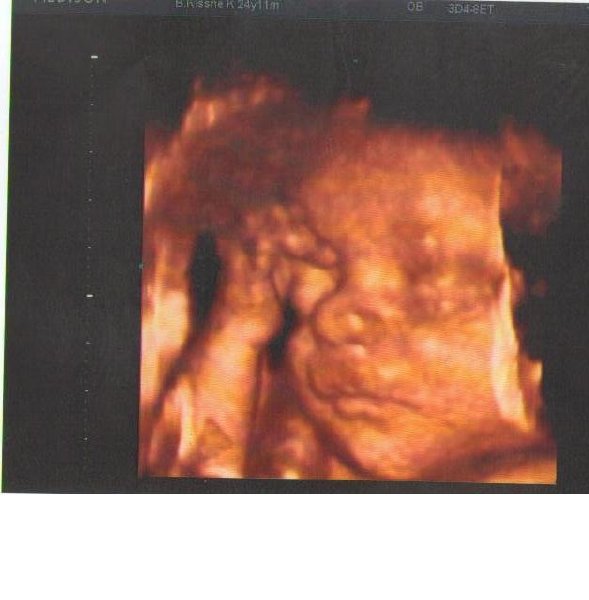

Judisz: Tudom hogy miről beszélsz. Amikor összejöttünk a férjemmel a 2. hónapban kirúgott mert anyósomék tele beszélték a fejét, azóta is nagyon "jó" a kapcsolatunk bár ennek ellenére sokat segítettek. Én viszont nem mondanám, hogy megneveltem a férjem. az olyan lenne mintha valami torzszülött lenne. Inkább egymáshoz csiszolodtunk. Nem csak neki hanem nekem is voltak rossz tulajdonságaim amin változtattunk. januárban töltjük be a 8. évünket, de volt jó is rossz is. 24. hét körül voltam 4D de akkor még nagyon csontos volt Bogi szóval most késöbbre tervezem kb 34-36 hét körül.

Pöcök: a 12 hét után fölösleges még 4D-re menni és a 24 hét körül voltam és még akkor is nagyon csontos volt. Most biztos hogy a 34-36 hét körül fogok menni hogy minnél több apróság látszodjon.

Én a 4dre úgy gondoltam 24-28 között megyek. ahogy elnéztem a képeket akkor már egész jól láható.